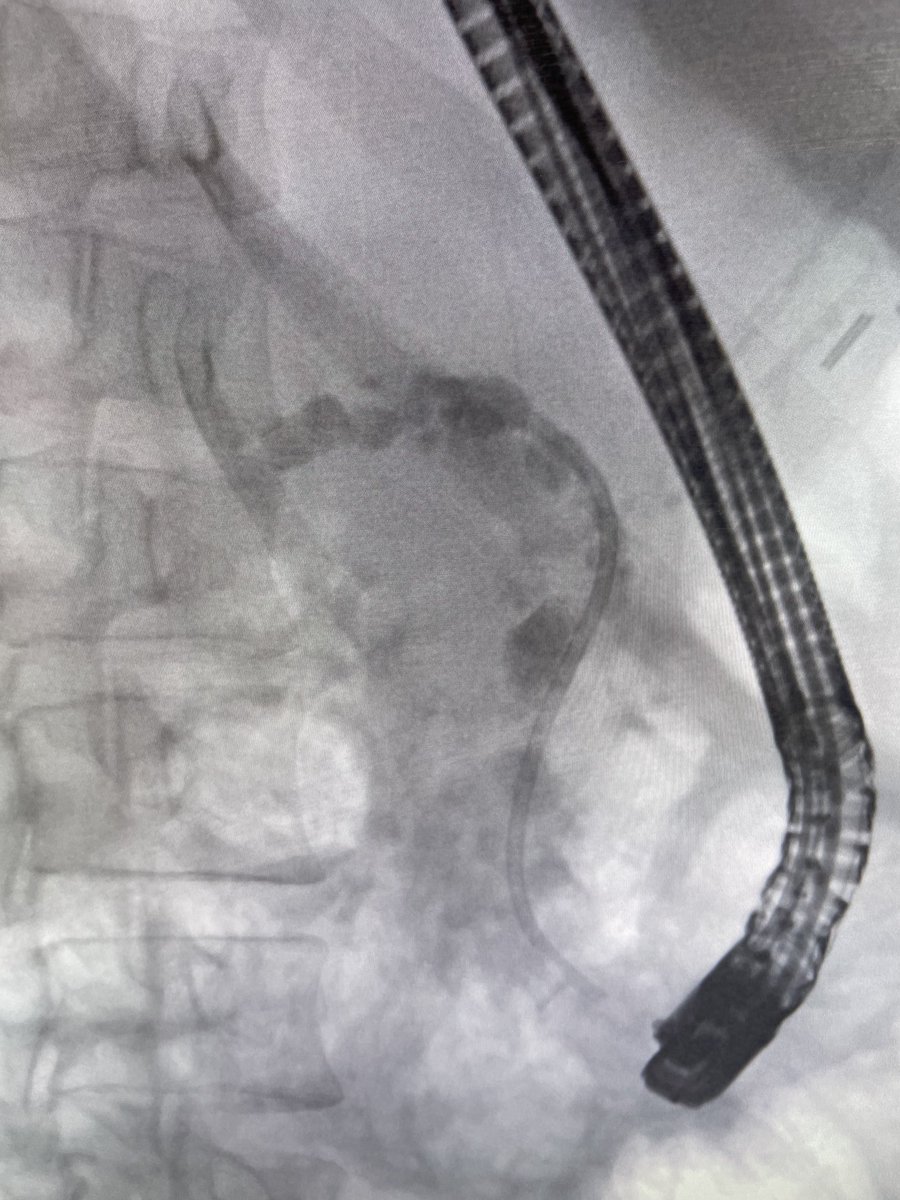

More hard-core chronic pancreatitis. Pancreatic sphincterotomy. Many stones removed. Many stones to go! #gitwitter #pancreas Aslak Gottlieb GIE Prof John Leeds Neal Mehta Scot Michael Lewey